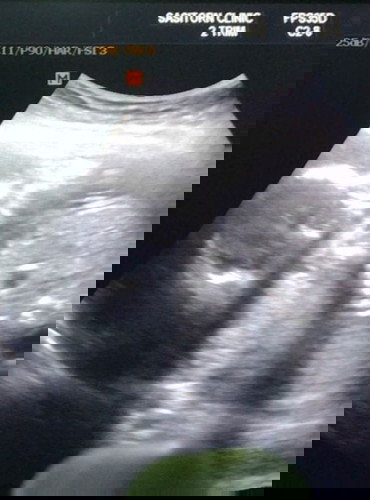

19Week2Day

วันนี้ไปอุลต้าซาวมา คุณหมอบอกว่า80%น้องเป็น ผู้หญิง 80%นี้น่าจาผู้หญิงชัวใหม้ค่ะคุณแม่มีความดีใจมากเพราะคนแรกผู้ชายนี่ก้อท้อง2จร้า กำหนดคลอด13มีนา แม่ๆคนไหนรู้เพศกันบ้างค่ะและกำหนดคลอดเดือนมีนาพร้อมกันบ้าง